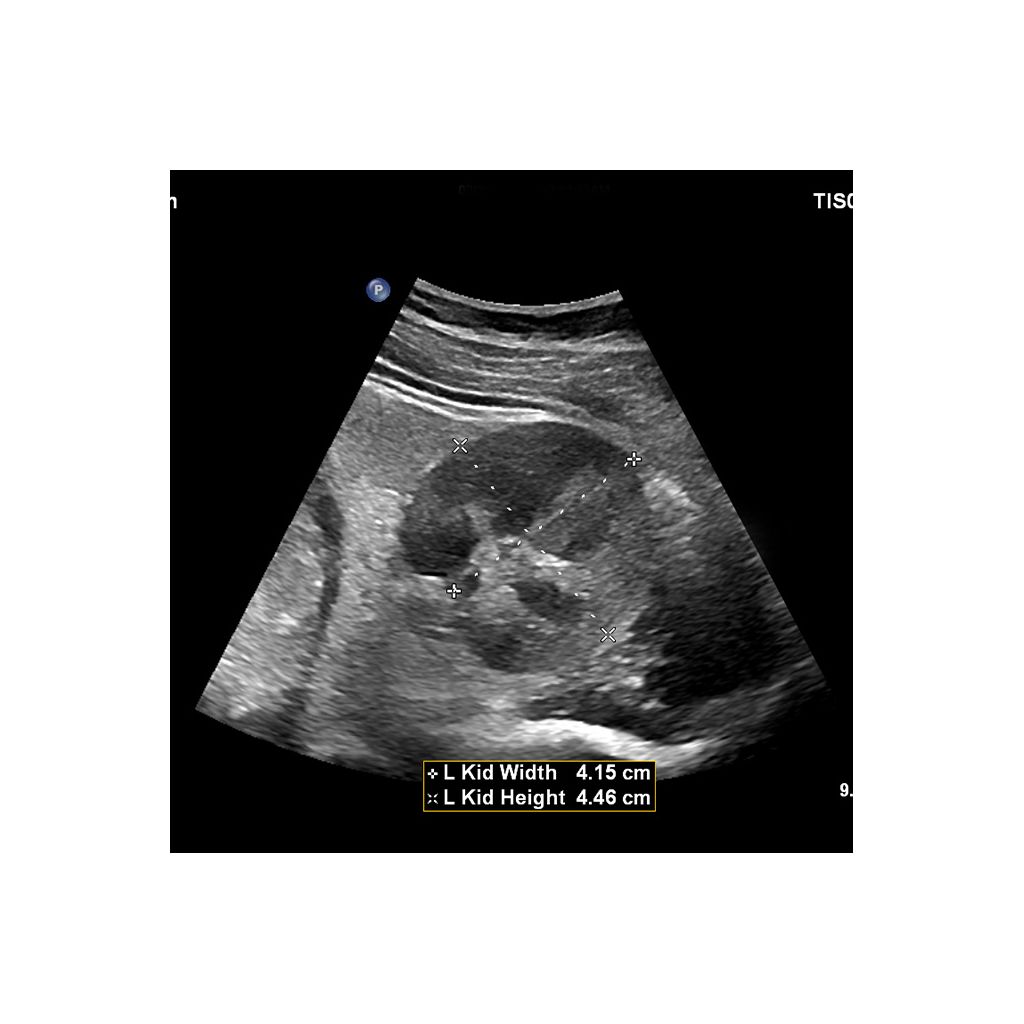

AI-driven Auto Measure Abdomen - Philips